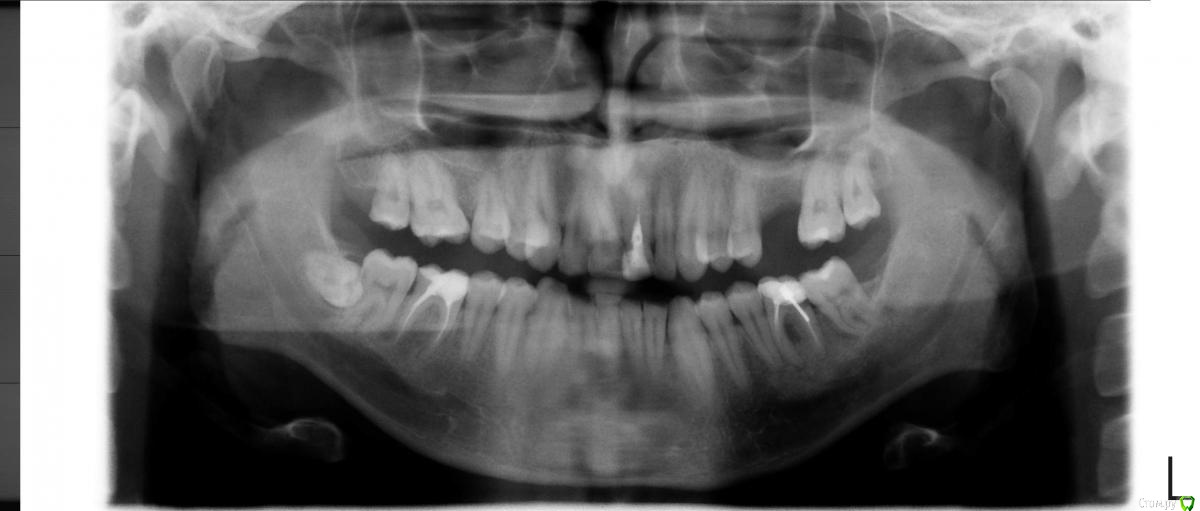

super Опубликовано 11 января, 2016 Поделиться Опубликовано 11 января, 2016 Доброго времени суток! Удаляю два зуба (снимки прилагаются). Будет ли возможность поставить импланты через несколько лет, если я откажусь от костного материала?В стоматологии расписали план, костный материал идёт опционально. Дескать, можно и без него, но лучше с ним, если планируете импланты (а я планирую через 2-3 года). Дополнительная информация:* Костный материал «БИ-ОСС» 0,5 гр.* 6-ка: пломба вылетела вместе со штифтом (снимок старый). Стоматолог сказал, что без шансов, надо удалять.* 7-ка: в 2-х стоматологиях сказали, что кариес корня и рекомендовали удалить. Спасибо :-) Ссылка на комментарий

diesel87 Опубликовано 11 января, 2016 Поделиться Опубликовано 11 января, 2016 Удалите правую нижнюю восьмерку, пока она не сделала тоже самое с правой семеркой. Ссылка на комментарий